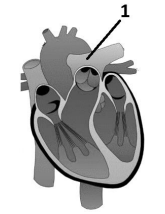

Observe a representação do coração humano.

A estrutura assinalada com o número 1 corresponde

A estrutura assinalada com o número 1 corresponde